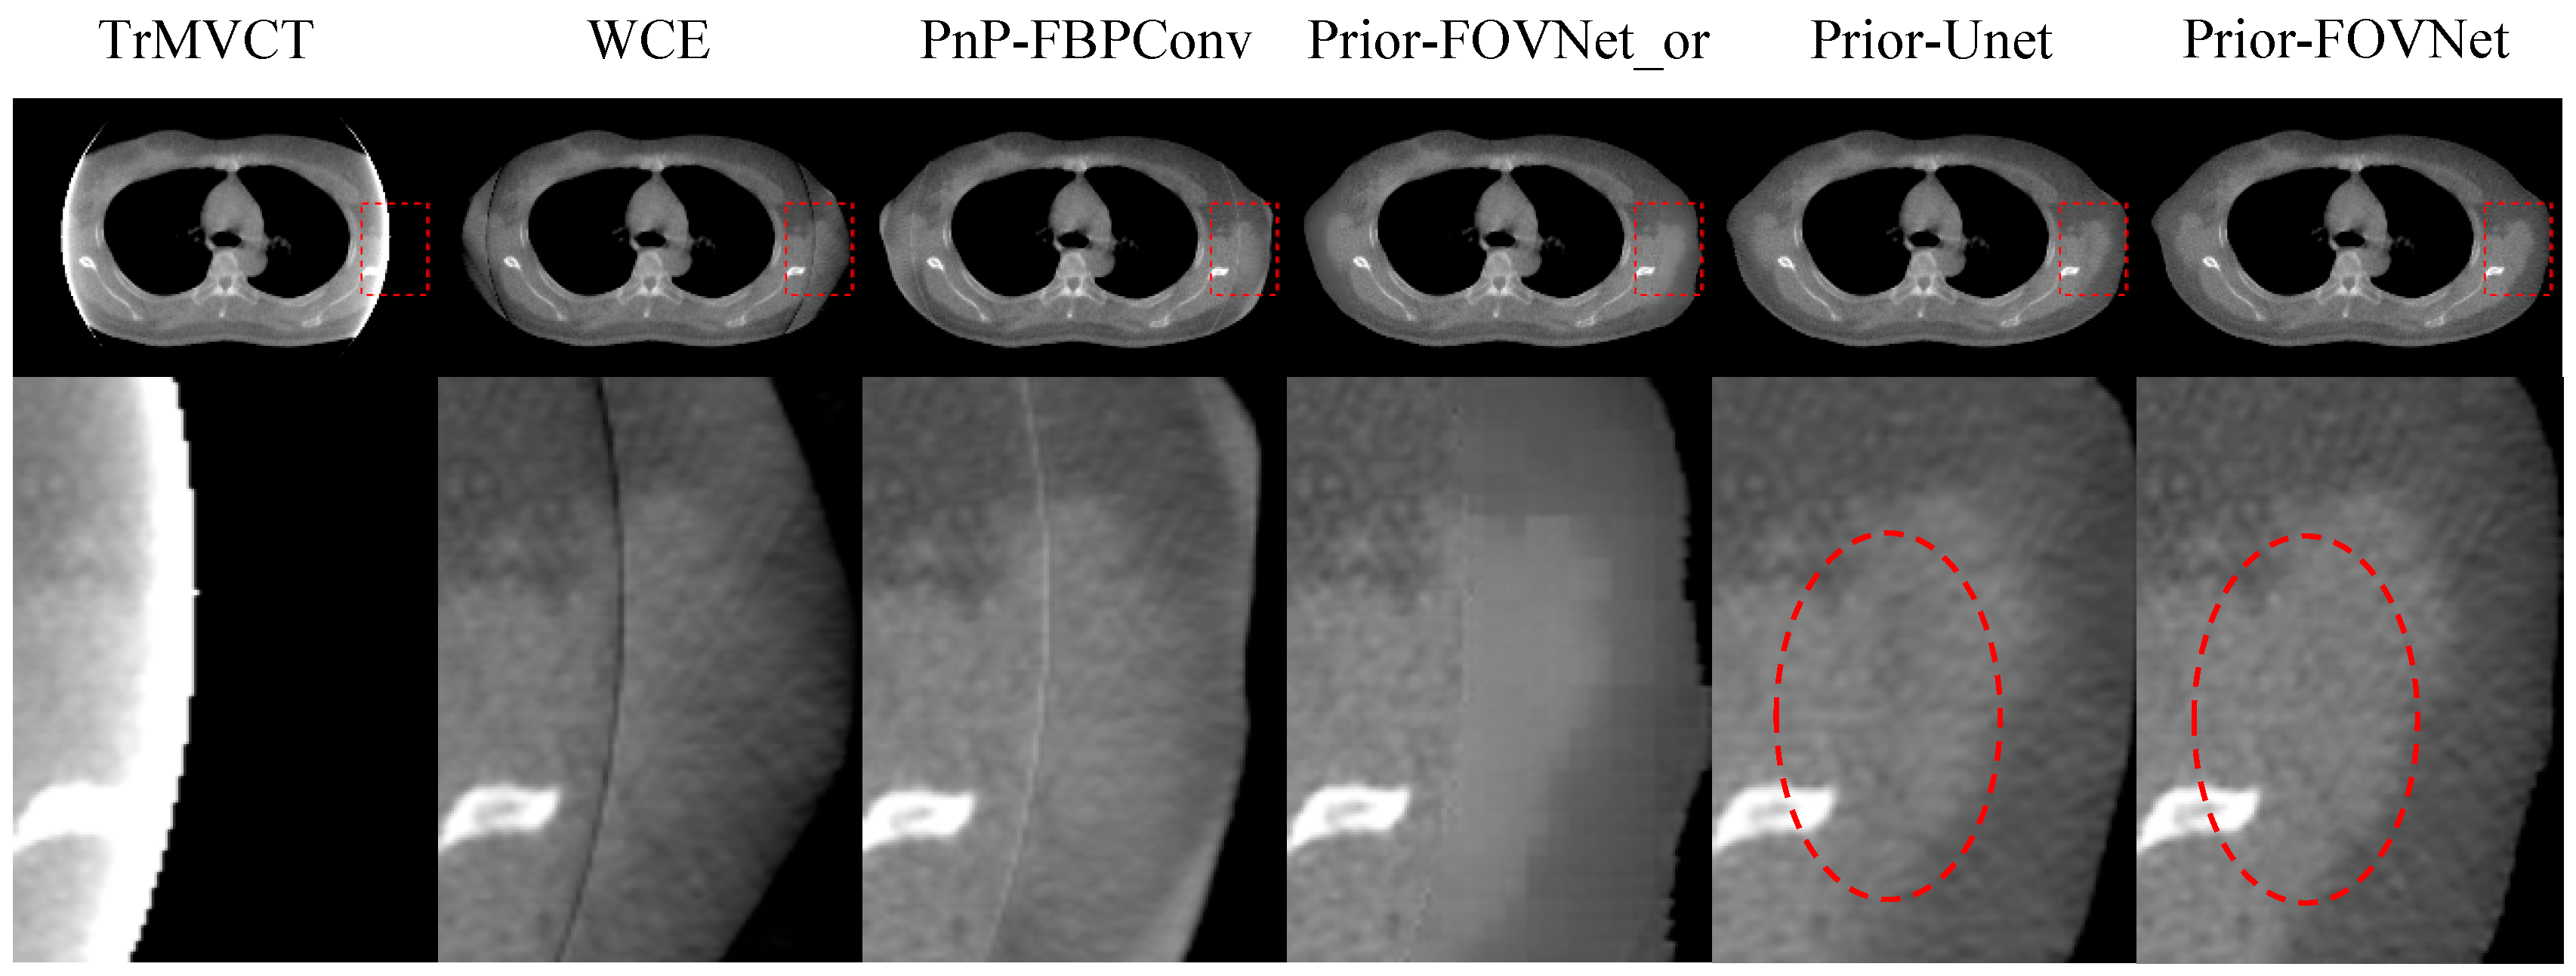

4.4. Ablation Study